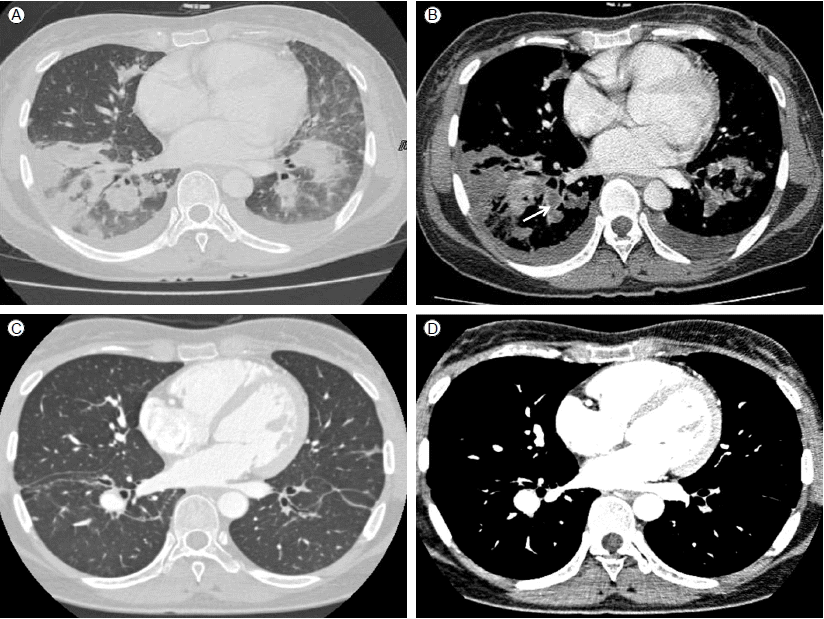

Figure 2.

Cardiac transthoracic echocardiography shows two oscillating echogenic lesions on the superior vena cava wall (0.1 × 1.25 cm, 0.18 × 0.82 cm) (asterisk).

환 자: 32세, 여자주 소: 3주간 지속되는 발열현병력: 내원 6주 전 파라콰트 종류인 그라목손(gramoxone) 음독으로 타병원 응급실에 입원하여 위 세척 및 대퇴정맥 이중내강 카테터를 통한 응급 혈액투석을 시행하였다. 그라목손으로 인한 폐 섬유증을 예방하기 위해 prednisolone 1 mg/kg 1일 1회 및 cyclophosphamide 충격요법을 하였으며 치료 시작 2일 후부터 경구 prednisolone 50 mg 1일 1회 요법으로 바꾸어 복용하였다. 환자는 그라목손 음독으로 인하여 구강 궤양이 발생하였으며 경구 섭취가 힘들어 우측 쇄골하정맥 카테터를 삽입하여 완전 정맥 영양을 시행하였다. 입원 21일째부터 발열이 동반되어 시행한 혈액배양 검사에서 Candida tropicalis가 배양되어 입원 25일째에 중심정맥 카테터를 제거하고, 경구 prednisolone 25 mg/day로 감량하면서 fluconazole 800 mg 부하용량 정맥주사 투여 후 400 mg 24시간 간격으로 정맥주사하기 시작하였다.입원 29일째 단순 흉부 방사선 사진에서 우측 하엽에 폐렴 소견이 확인되어 원내 획득 폐렴 가능성을 고려하여 항생제 치료를 시작하였고 입원 36일째에는 경구용 스테로이드 복용도 중지하였다. 그러나 여전히 Candida tropicalis에 의한 진균혈증과 39도 이상의 발열이 지속되고 이전에 없던 호흡곤란을 호소하여 입원 36일째 fluconazole은 중지하고 amphotericin B 1 mg/kg 24시간마다 정맥주사로 변경 후 입원 37일(진균혈증 발생 16일)에 본원 응급실로 전원되었다.과거력: 약물 남용의 과거력은 없었으며, 심내막염 등의 병력도 없었다.개인력: 흡연력, 음주력은 없었다.신체 검사: 활력 징후는 혈압 140/89 mmHg, 맥박수 120회/분, 호흡수 19회/분, 체온 39℃이었으며 의식도 명료하였다. 만성 병색을 나타내고, 폐 양측 하엽에서 수포음이 청진되었으며 심음은 규칙적이고 잡음이 청진되지 않았다. 좌안의 시력 저하를 호소하였으며 다른 신경학적 증상은 보이지 않았다. 양측 상 하지에 연부조직 감염을 의심할만한 소견도 보이지 않았다.검사실 소견: 말초혈액검사에서는 백혈구 8,020/mm3(호중구 79.5%, 림프구 13.1%), 혈색소 8.3 g/dL, 혈소판 231,000 /mm3으로 호중구 비율 증가 및 빈혈이 있었다. 적혈구 침강 속도 63 mm/hr, C-반응단백 26.94 mg/dL로 증가되어 있었다. AST/ALT 44/60 U/L으로 약간 상승되어 있었고, 알부민 2.5 g/dL로 감소하였으며, 신기능은 정상이었다. 고배율 시야 소변 검사에서 현미경적 혈뇨를 동반하였으며 그 외 검사에서는 특이 소견이 없었다. 진균혈증 발생경과 17일에 시행한 말초 혈액배양 검사 3쌍은 모두 음성이었고 이후 시행한 모든 말초 혈액배양 검사도 배양 음성이었다.방사선 소견: 단순 흉부 방사선 사진에서 폐 양측 하엽에 반점형 침윤(patchy infiltration) 폐렴 소견이 보였다. 입원 2일(진균혈증 발생 18일)째 장기간 진균혈증을 보인 것에 대하여 흔한 합병증인 심내막염 발생을 확인하기 위해 경흉부 심장초음파 검사를 시행하였으며 좌심실 수축기 기능이나 심근벽운동 장애는 없었고 심내 증식증도 없었다.입원 6일(진균혈증 발생 22일)째까지도 39℃ 이상 열이 지속되어 흉부, 복부 컴퓨터단층촬영술(CT)을 시행하였다. 흉부 CT에서 양측 폐야에 다발성 결절 음영이 있고 기관지 주위 반점형 경화성 병변(peribronchial patchy consolidation) 및 젖빛유리혼탁(ground glass opacity), 간질비후(interstitial thickening)가 관찰되었으며 우하분엽 폐동맥과 그 하방 및 좌하엽 폐 동맥과 그 하방으로 거의 폐 동맥의 내강 대부분을 차지하는 다발성 혈전 색전증도 관찰되었다(Fig. 1A). 입원 7일(진균혈증 발생 23일)째 경흉부 심장초음파 추적검사에서 0.1 × 1.25 cm, 0.18 × 0.82 cm의 진동하는 에코 발생 종괴(oscillating echogenic material) 2개가 우심방의 상대정맥 삽입부에서 관찰되었다(Fig. 2).폐 혈전색전증의 정확한 평가를 위해 심부 정맥 혈전 컴퓨터단층촬영(DVT-CT)을 시행하였으며 폐동맥 혈전이 우하엽 폐동맥과 그 하방 그리고 좌하엽 폐동맥과 그 하방으로 확인되었다(Fig. 1B). 입원 22일(진균혈증 발생 38일)째 추적 관찰한 DVT-CT에서는 이전과 비교하여 양측 폐에 다발성 결절 음영과 기관지 주위 경화성 병변은 일부 호전되었으며 양측 폐동맥 혈전 색전은 조금 감소하였으나 여전히 남아있었다.안과 검사 소견: 전원 당시 좌안의 시력 저하로 안과에 협진 의뢰하였고 망막의 출혈과 침윤 소견이 보여 칸디다 내인성 안내염으로 진단하였다(Fig. 3).치료 및 경과: 타병원에서 fluconazole 투여하였으나 호전보이지 않아 fluconazole 내성 고려하여 진균혈증 발생 15일부터 amphotericin B를 1 mg/kg 24시간마다 정맥주사로 투여하기 시작하였다. 전원 후에도 발작적인 호흡곤란이 지속되고 폐렴의 호전이 없으며 39도 이상 발열이 지속되어 약열의 가능성 고려하여 입원 4일(진균혈증 발생 20일)째 amphotericin B 투여를 중단하고 caspofungin 50 mg 24시간 마다 정맥주사로 변경하였다. 입원 6일째 호흡곤란과 양측 폐 동맥을 거의 다 폐쇄하는 다발성 색전으로 급성 폐 색전증에 준하여 wafarin과 enoxaparin 주사로 항응고 치료를 시작하였다. 항응고 치료와 caspofungin 총 21일 동안 치료 후 호흡곤란과 발열이 호전되며 C-반응단백도 처음 입원 당시 26.94 mg/dL에서 4.3 mg/dL까지 호전되어 환자의 경제적 부담을 고려하여 다시 amphotericin B 1 mg/kg/day로 변경하였다.Amphotericin B 25일간 총 누적용량 1,290 mg 투여 후 흉부 단층 촬영을 시행하였으며 다발성 결절 음영과 기관지 주위 반점형 경화 병변의 호전 소견 보여(Fig. 1C) fluconazole 400 mg/day 경구 투약으로 변경하였다. 진균혈증 발생 103일 째 시행한 흉부 혈관 조영 컴퓨터단층촬영(chest CT angiography)에서 양측 하분엽 폐동맥 분지의 혈전 호전 소견이 보였다(Fig. 1D). 진균혈증 발생 109일째 안과 추적검사를 시행하였고 칸디다 내인성 안내염은 모두 호전되어 더 이상 병변은 관찰되지 않았다. 환자는 경구 fluconazole 400 mg/day 총 24주 동안 투여 후 치료를 종료하였다.